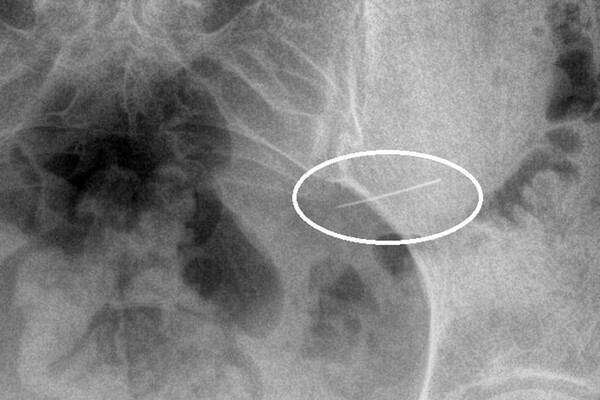

Пациентка вовремя обратилась за помощью, и бригада скорой доставила ее в стационар. Рентген брюшной полости показал инородное тело в желудке. Врачи первого хирургического отделения подготовили ее к экстренной операции, после чего с помощью современного оборудования эндоскописты аккуратно удалили опасный предмет, не допустив осложнений.